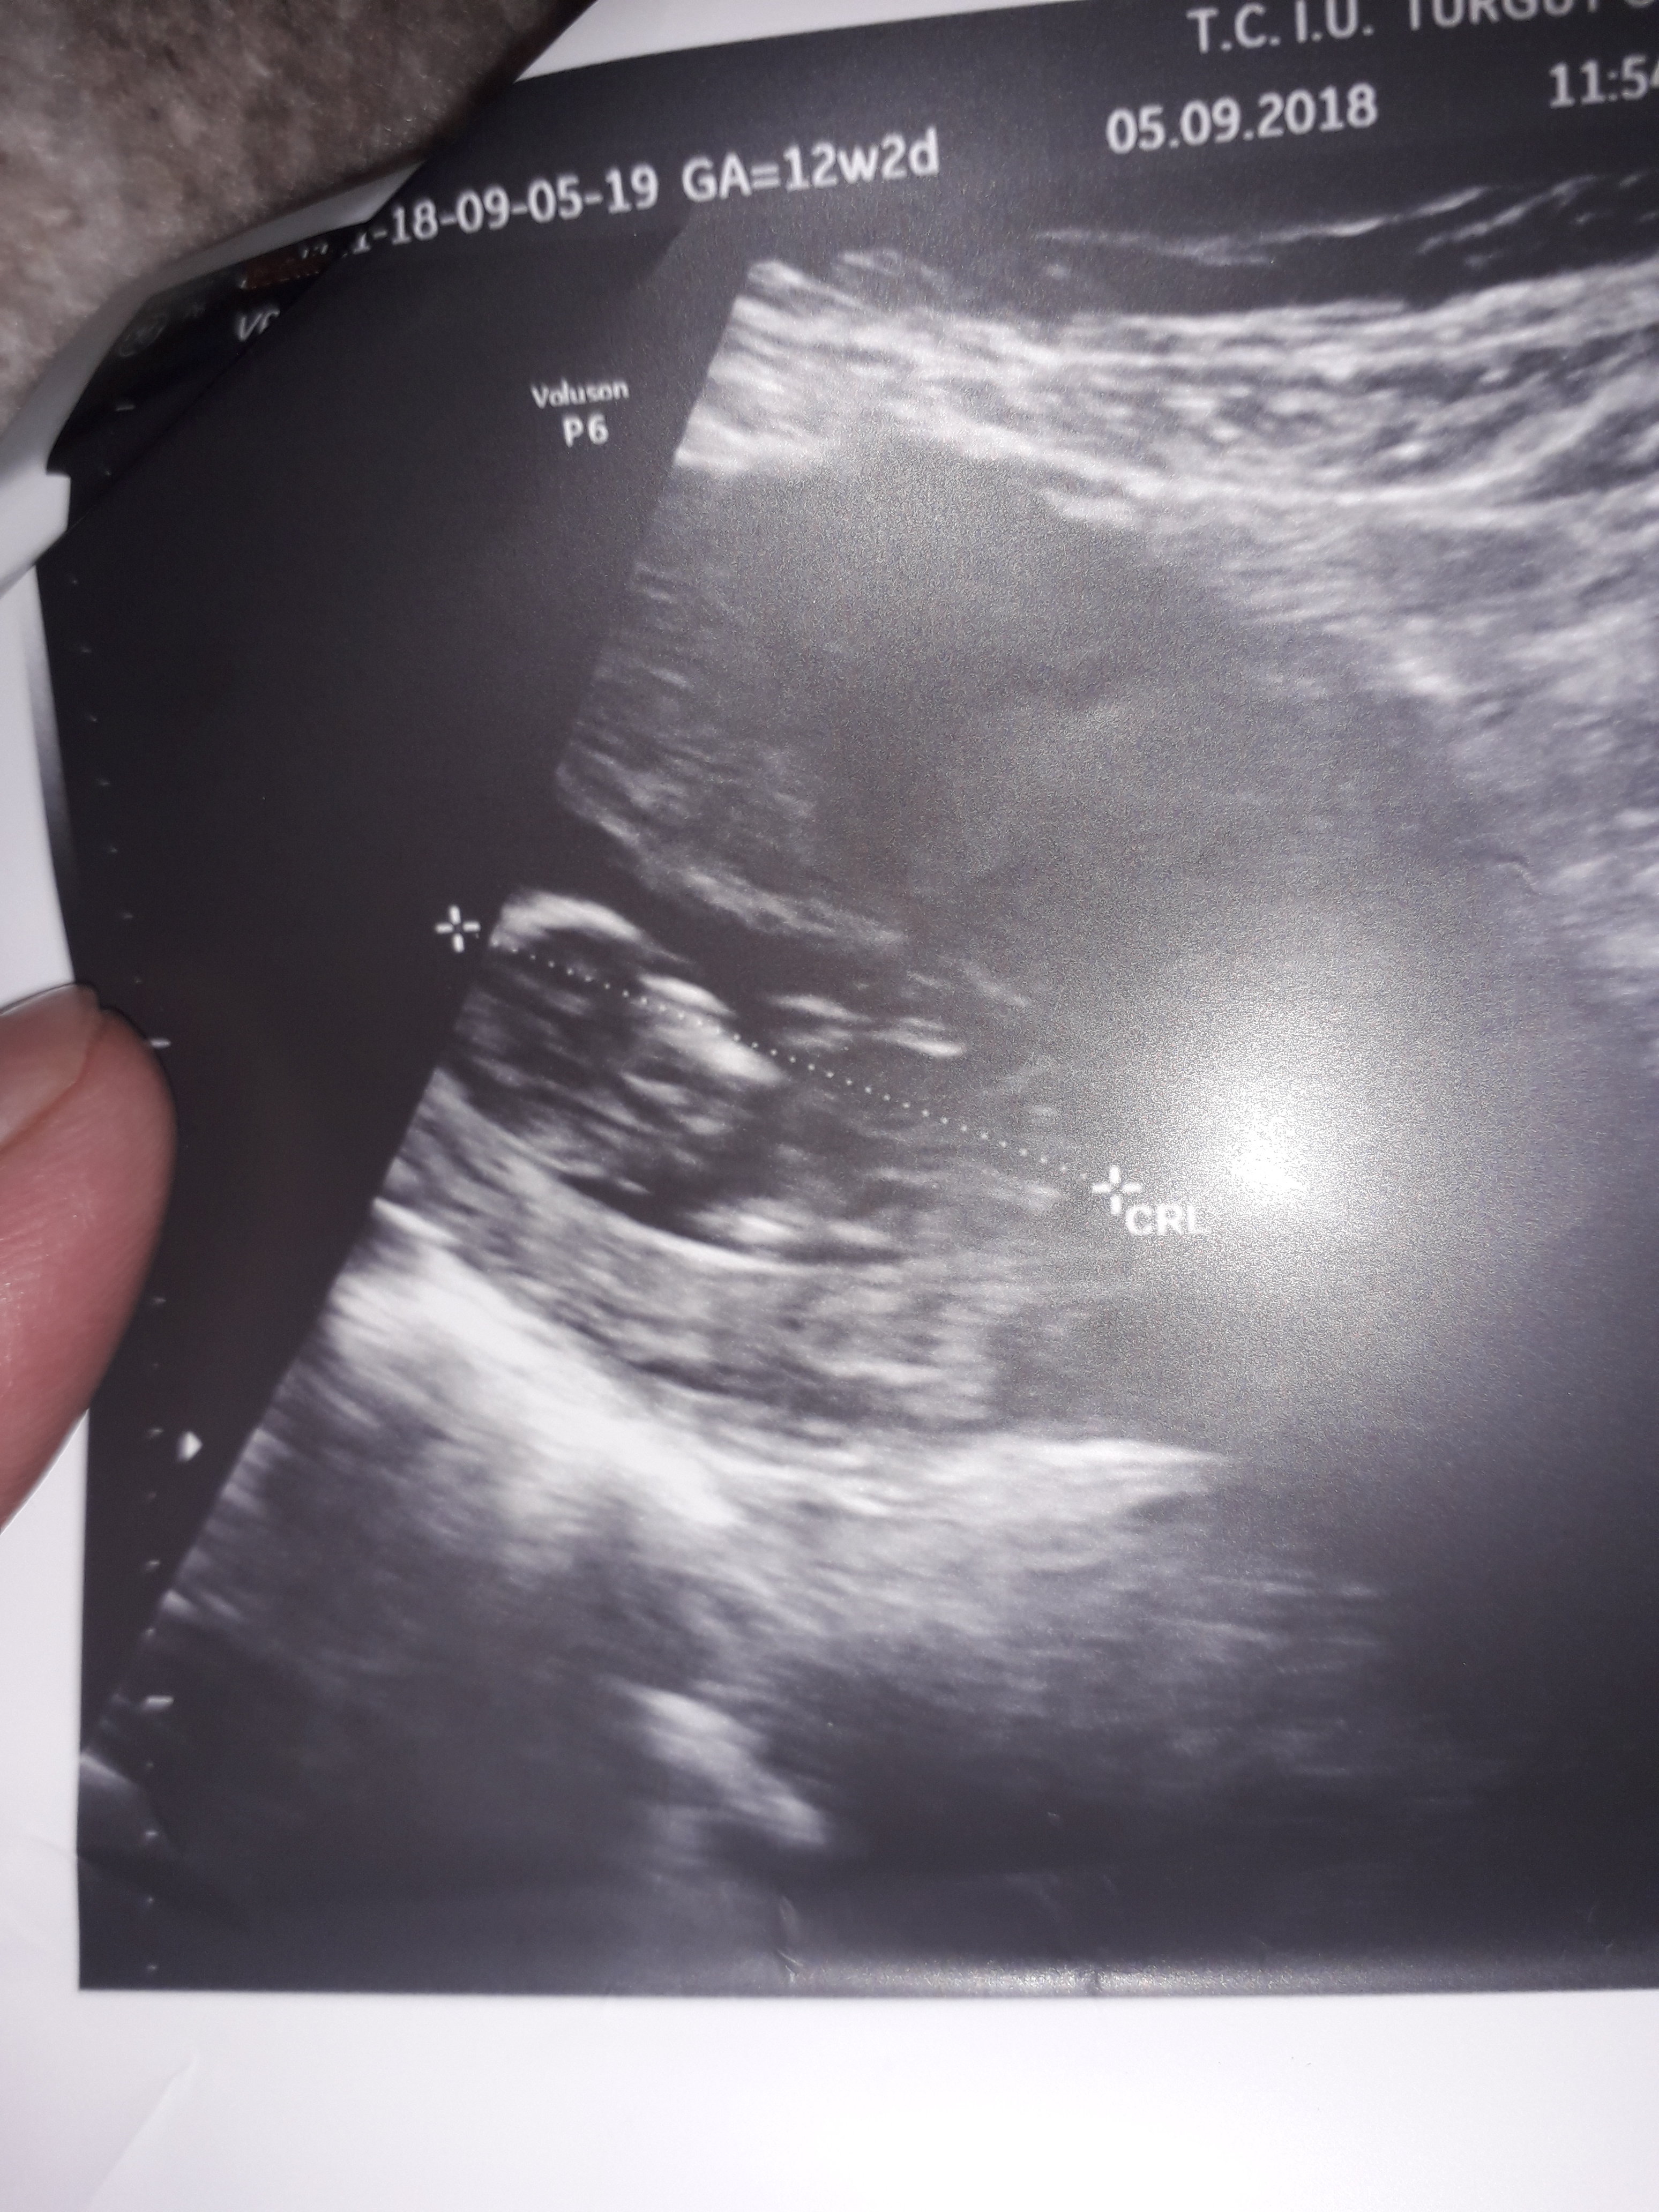

Dun malatyada verildi 12 +4 gunluk lutfen yorumlayin

nub çıkıntısının üzerinde imleç var cinsiyet anlaşılmıyor ilk sayfayı incelemenizi öneriyorum görselin kalitesi konu içinde yer alan görselle aynı olmalıdır.

Görsellerde nub çıkıntısı belli değil . Ultrasonu yapan doktor cinsiyeti hakkında bilgi vermiştir mutlaka ama şunu belirtmeden geçmeyeyim. Bu haftalarda cinsiyet tahmininde yanılma payı çok yüksek 17-19 ve 20 ci haftalarda bebeğin cinsiyetini net olarak öğrenebilirsiniz.